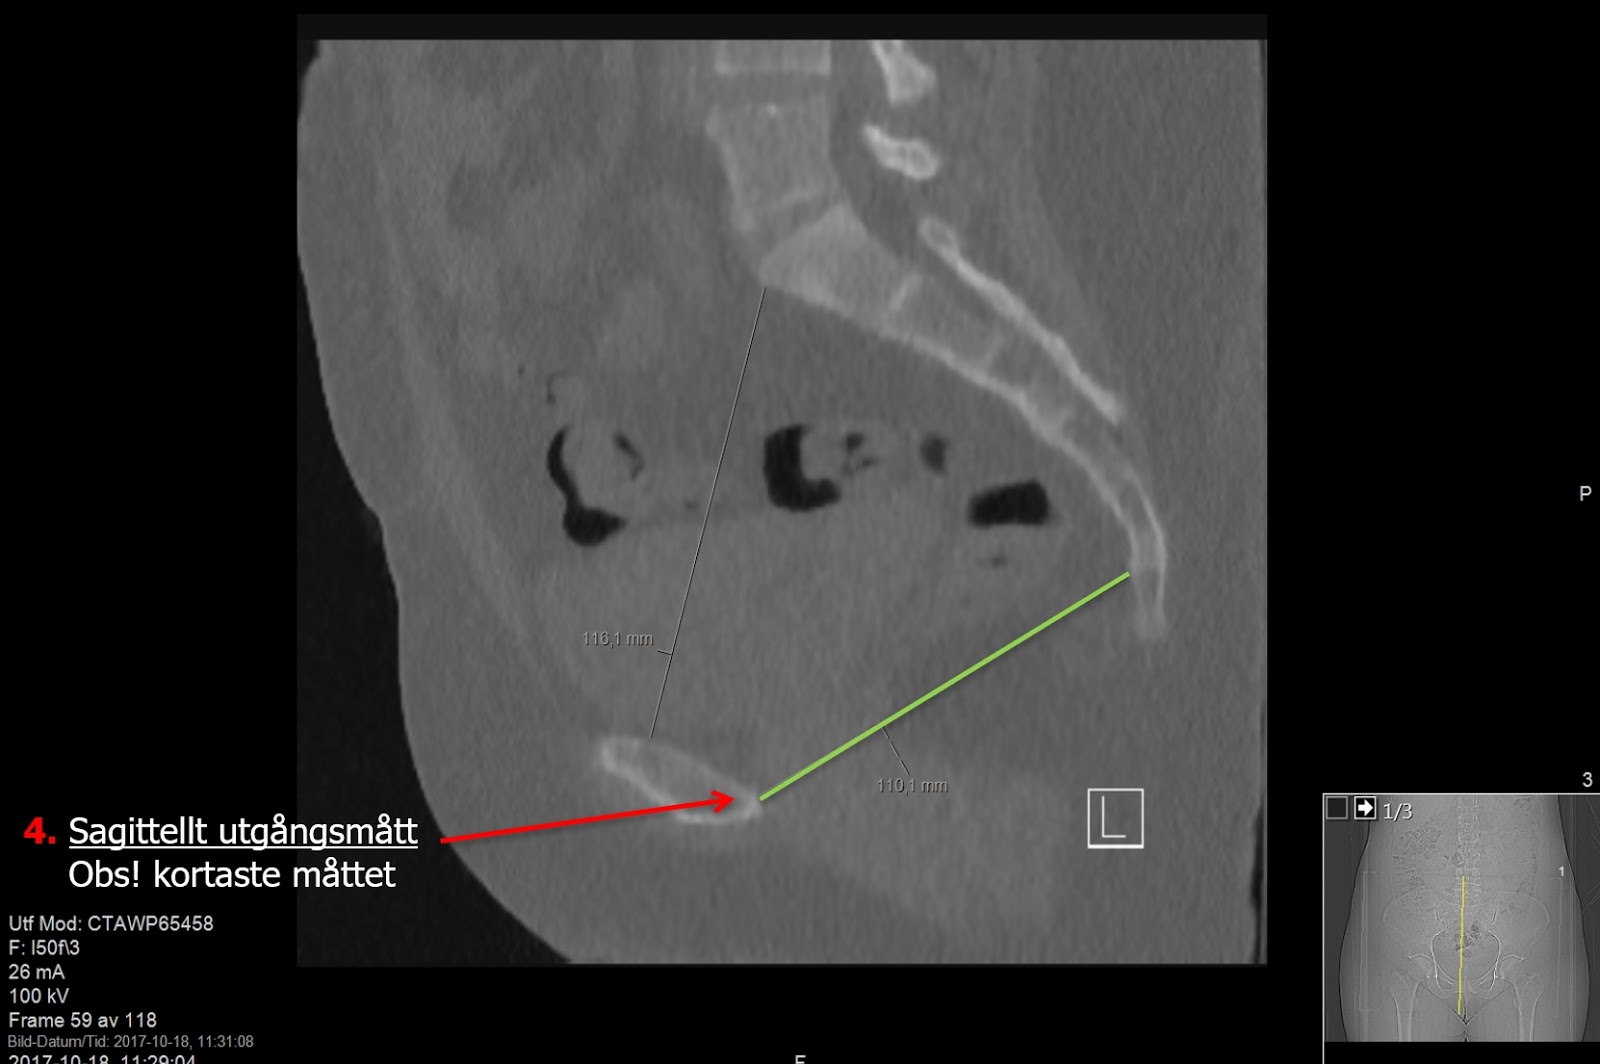

On sagittal reconstruction measure Sagittal Inlet Diameter (Sagittellt ingångsmått) as shortest distance between posterior part of symphysis pubis and promontorium (S1). As well as Sagittal Outlet Diameter (Sagittellt utgångsmått) as shortest distance between posterior part of symphysis pubis and fist mobile joint between sacrum and coccyx.

Sagittal reconstruction for Sagittal Outlet Diameter - measure the shortest between posterior part of symphysis pubis and fist mobile joint between sacrum and coccyx.